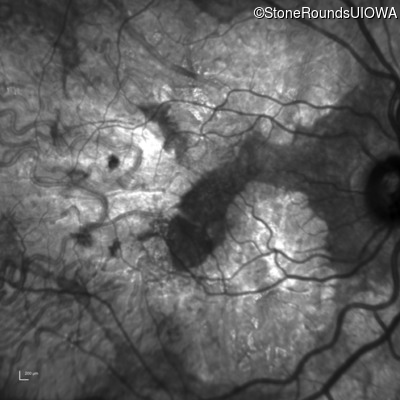

Age at visit: 51 years

OD OS

This 51 year old woman first experienced some abnormality in her distance vision when she was 27 years old. She feels that her vision has been stable since that time.